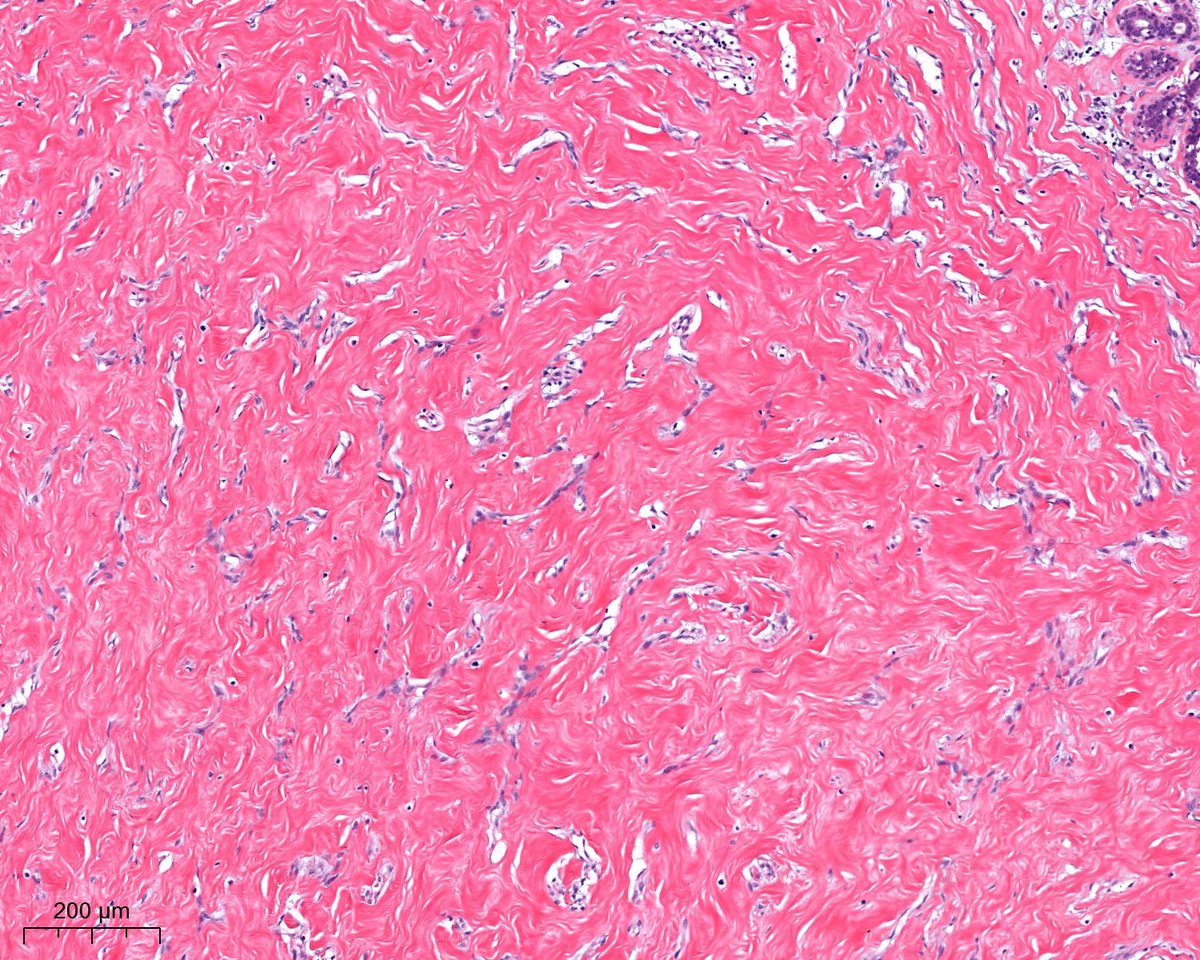

What is this? - easy; Where are we? - difficult? 😃Dr. Luca Olaleke Folaranmi Tania Labiano Aurélien Morini, MD, MSc 🇫🇷🇪🇺💙💛 Celina Stayerman MD 🔻Nusrat Zahra🔻🇵🇸 @miss_me1986 Gonzalo De Toro Tristan Rutland MBBS FRCPA IFCAP GI James Anandi Lobo, MD Angel Panizo MD, PhD 🇪🇸 🔬 Sumanta Das Lorand Kis Laura G. Pastrián MD Carlos Miguel Ruiz Carlos Nieves

benign nodule of the breast😃#breastpath Dr. Luca Olaleke Folaranmi Alexander Damron, MD Liza Quintana, MD Anne Grabenstetter Tania Labiano Jenny Pincus, MD Aurélien Morini, MD, MSc 🇫🇷🇪🇺💙💛 Celina Stayerman MD 🔻Nusrat Zahra🔻🇵🇸 @miss_me1986 Gonzalo De Toro Tristan Rutland MBBS FRCPA IFCAP Sumanta Das Israh Akhtar Khan Lorand Kis Carlos Miguel Ruiz Carlos Nieves